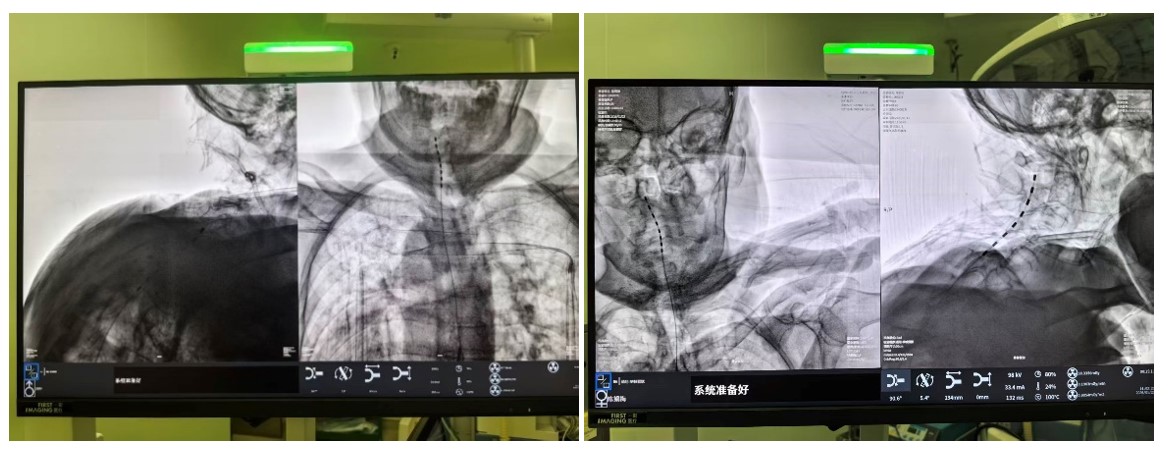

C臂透视示术中电刺激已成功置入。

手术在局麻下进行,老人全程清醒。术中,当电极启动测试时,陈奶奶激动地反馈:“麻到了!颈椎和肩胛都不痛了!”这种即时反馈确保了电极能够百分百覆盖痛区。术后一周,两位老人的疼痛视觉模拟评分(VAS,0分为无痛,10分为剧痛)从术前的8-9分骤降至2-3分,睡眠质量和情绪状态得到了质的改善。